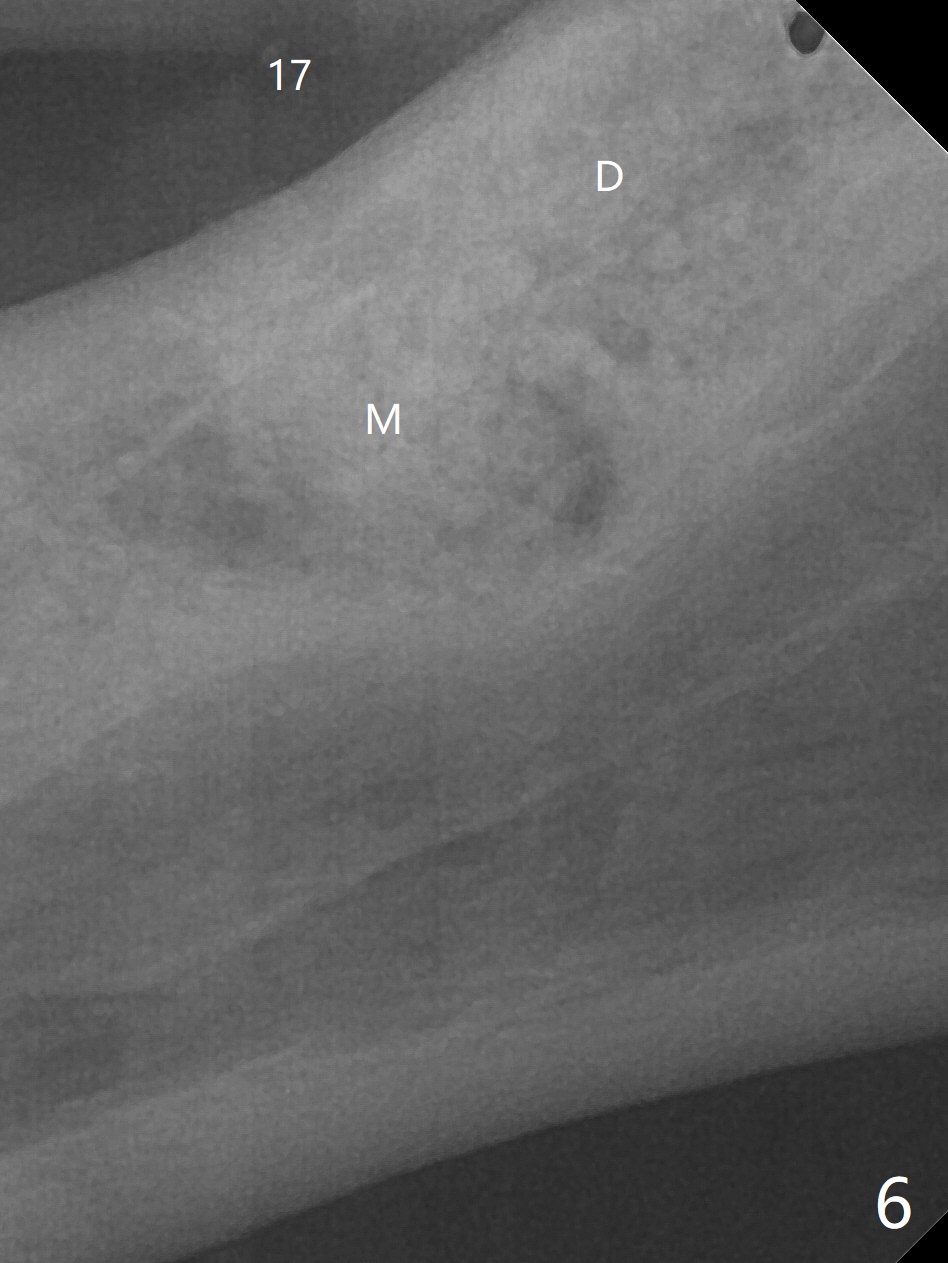

A 84-year-old man (uncontrolled diabetes) requests extraction of terminal teeth (#17, 20-22) for complete denture (Fig.1-3). He does not have finance for implants now. After extraction and debridement, 1 cc of Bond Apatite is applied to the sockets (Fig.4-6). The sockets at #20-22 are primarily closed with 4-0 PGA (Fig.7), while that of #17 with 4-0 Chromic gut suture over Osteogen Plug (a type of Collagen Plug, Fig.8). PGA sutures remain in place (Fig.9,10), while Chromic Gut ones dissolve 7 days postop (Fig.11). The ridge at the extraction sites remains robust 2 months postop (Fig.12). The sockets seem to remain radiopaque 2 months postop (Fig.13).